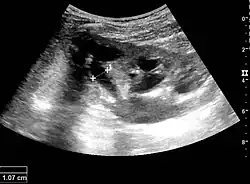

One of the primary indications for referral to US evaluation of the kidneys is evaluation of the urinary collecting system. Enlargement of the urinary collecting system is usually related to urinary obstruction and can include the pelvis, the calyces and the ureter. Hydronephrosis is seen as an anechoic fluid-filled interconnected space with enhancement within the renal sinus, and normally, the dilated pelvis can be differentiated from the dilated calyces.[1]

Several conditions can result in urinary obstruction. In both adults and children, masses, such as abscesses and tumors, can compress the ureter. In children, hydronephrosis can be caused by ureteropelvic junction obstruction, ectopic inserted ureter, primary megaureter and posterior urethral valve (Figure 13). In the latter, both kidneys will be affected. In adults, hydronephrosis can be caused by urolithiasis, obstructing the outlet of the renal pelvis or the ureter, and compression of the ureter from, e.g., pregnancy and retroperitoneal fibrosis. Urolithiasis is the most common cause of hydronephrosis in the adult patient and has a prevalence of 10%–15%.[1]

The hydronephrosis is typically graded visually and can be divided into five categories going from a slight expansion of the renal pelvis to end-stage hydronephrosis with cortical thinning (Figure 15). The evaluation of hydronephrosis can also include measures of calyces at the level of the neck in the longitudinal scan plane, of the dilated renal pelvis in the transverse scan plane and the cortical thickness, as explained previously (Figure 16 and Figure 17).[1]